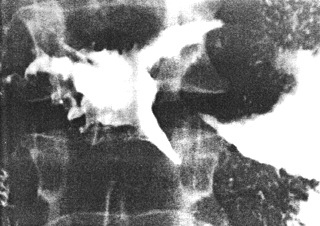

| Fig. 33.11.Case K.B. Constricting pyloric filling defect. Base of duodenal bulb normal. |

Case 33.12 E.L.J., 44 year old male. Radiology: 7.0 cm long constricting pyloric filling defect. Base of duodenal bulb normal (Fig. 33.12). Operation: large mass pyloric region with serosal spread. Duodenum appears normal. Widespread lymphatic metastases. Coeliac and para-aortic glands involved. Metastases in transverse mesocolon and spleen. Billroth II. Gastric histology: poorly differentiated adenocarcinoma (mucinous type with signet ring cells). Duodenal histology: spread into submucosa up to commencement of Brunner's glands. No infiltration of Brunner's glands or superficial mucosa.

![]() | |

| Fig. 33.12 A-D Case E.L.J. Constricting pyloric filling defect. Base of duodenal bulb normal. | |